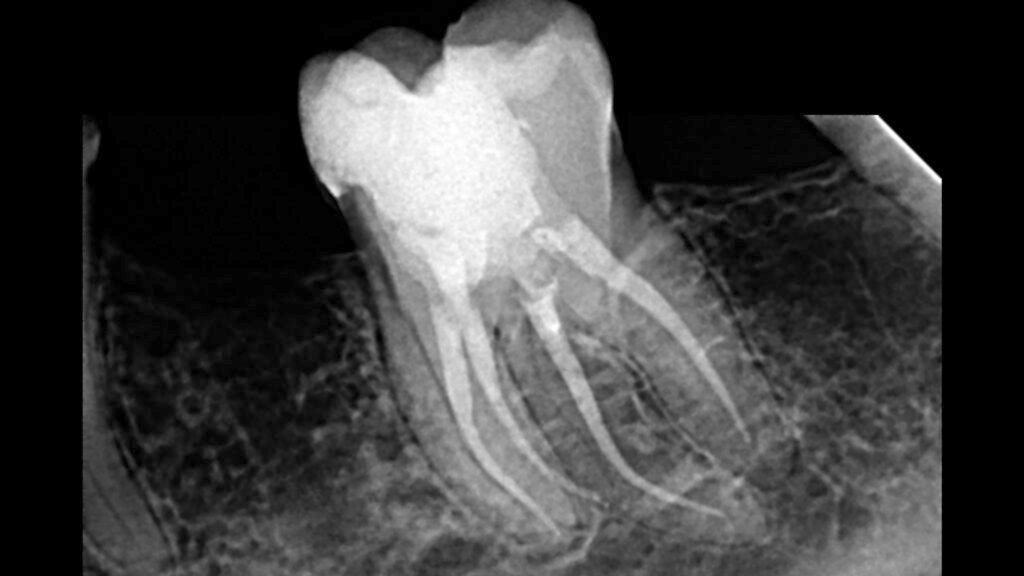

A 60-year-old female patient presented with persistent pain in a lower first molar. Clinical and radiological examinations revealed a long-standing cavity and severe calcification of the root canals, making cleaning, shaping, and filling highly challenging. Radiographs suggested an unusual root anatomy, with more than the typical two roots. During treatment, it was confirmed that the tooth had three roots and a total of four canals, a rare anatomical variation for a lower first molar.

Using advanced endodontic tools and techniques, all canals were successfully negotiated, thoroughly cleaned, shaped, and beautifully filled. The entire root canal procedure was completed in a single visit lasting approximately two hours. Following the root canal treatment, the tooth was restored with a composite restoration. The patient returned for a post-operative checkup after three days, reporting complete relief from pain and showing good clinical signs of healing.